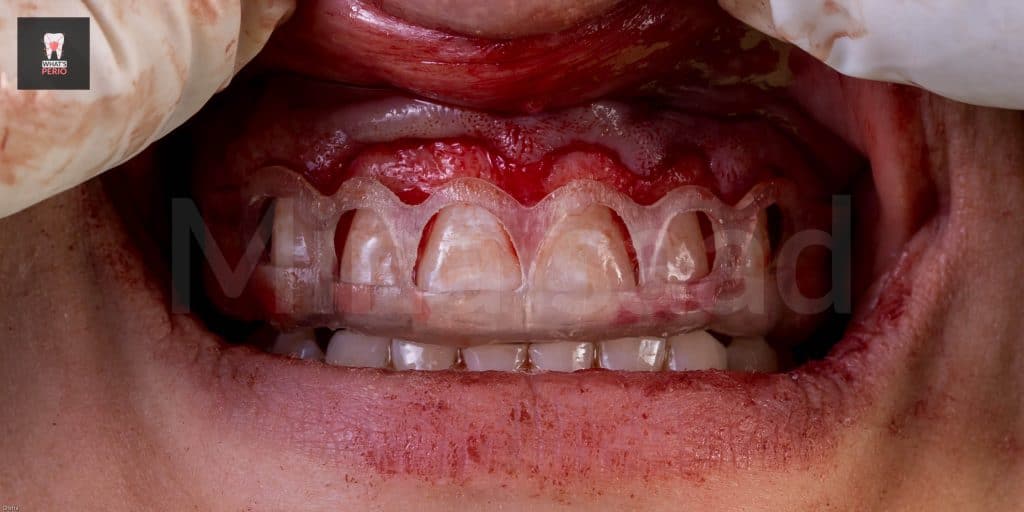

-External bevel gingivectomy was made while the guide in place.

-Internal bevel incision was made “envelope flap” to expose underlying labial plate of bone.